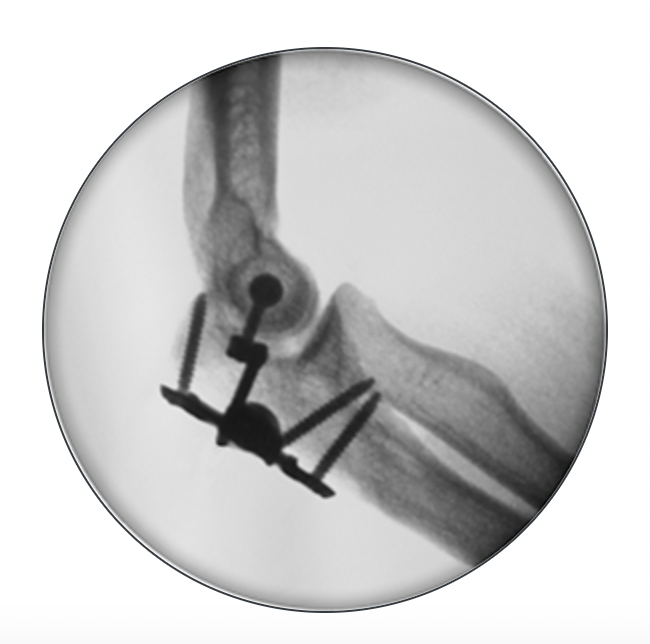

Compass Hinge Centre of Rotation

Lateral humeral pin Medial humeral pin Ulna pins

Anterior to radial nerve

Posterior to ulna nerve

Subcutaneous border of ulna

Compass Hinge Lateral XrayCompass Hinge AP Xray